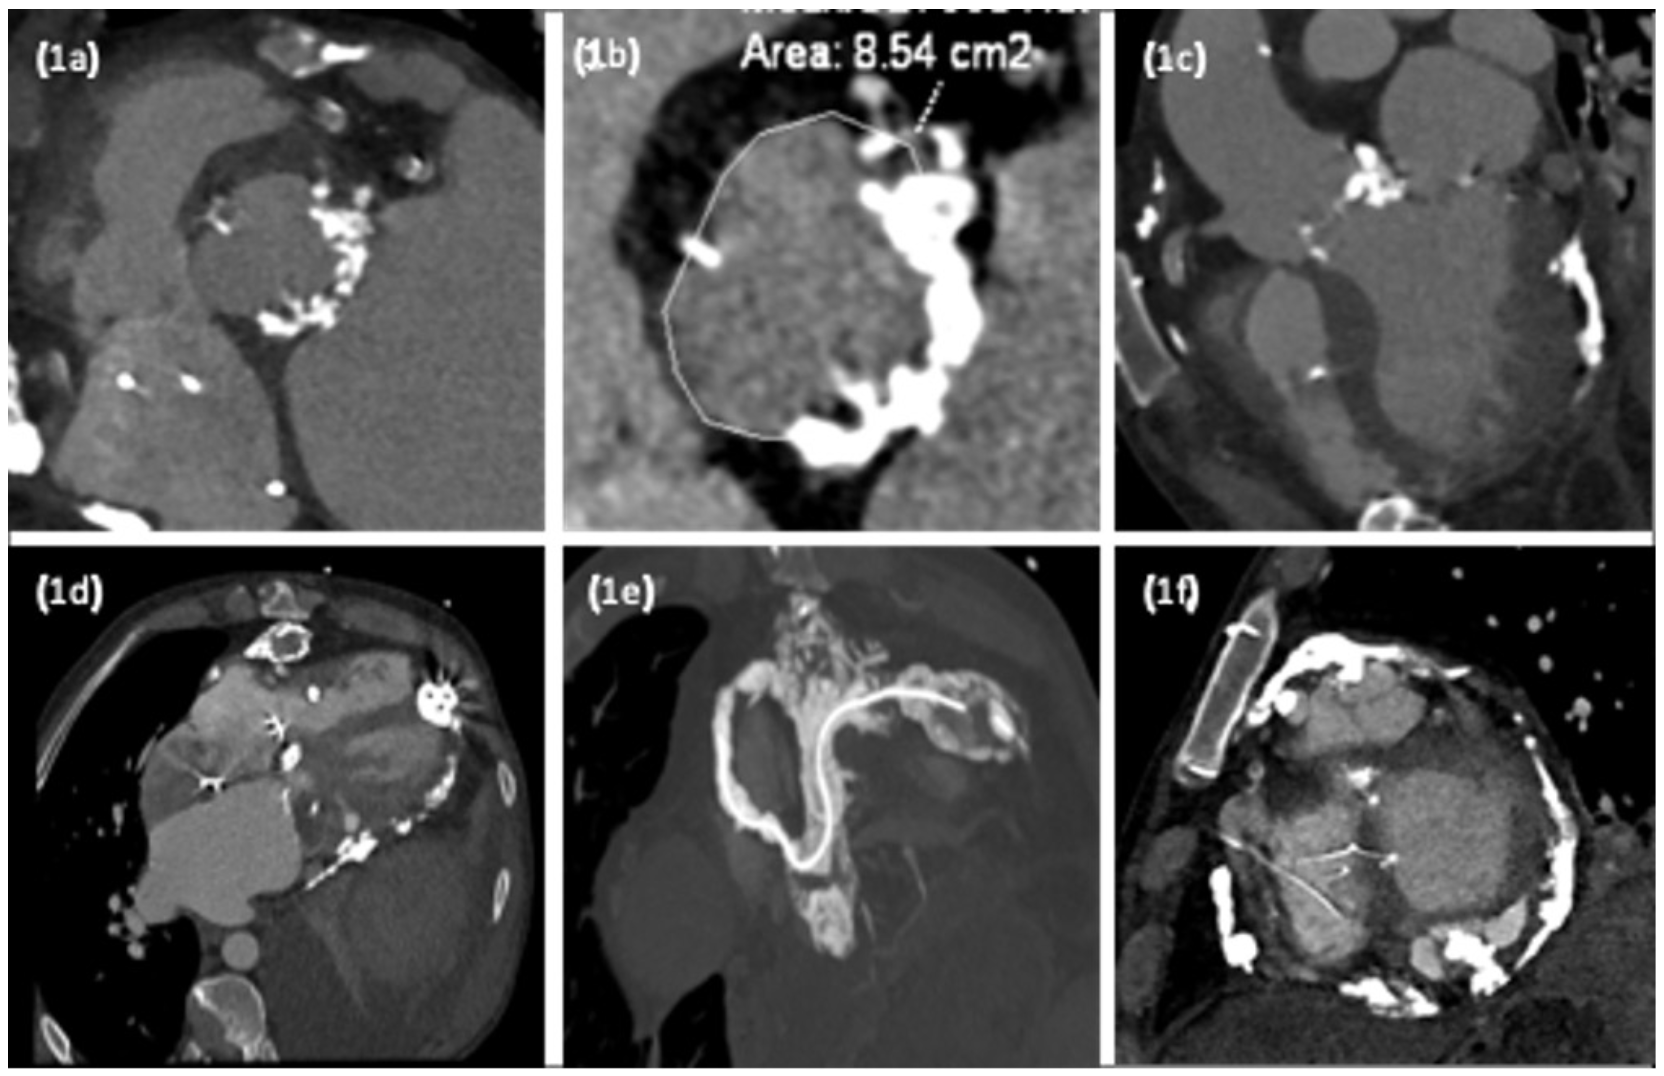

Gated cardiac computed tomography (Figure 1) revealed extensive eccentric calcification of the left ventricular outflow tract (LVOT) extending into the mitral valve leaflet and a large aortic annulus (33 mm; mean annular diameter/area, 854 mm2). This is larger than all recommended manufacturer annular size limits, although observational data support the use of both Edwards Sapien 3 and Medtronic Evolut R in such annuli. In this case, the extent of LVOT calcification significantly increased the risk of annular rupture with a balloon-expandable valve. Hence, a self-expanding, 34-mm Evolut R valve was chosen and deployed successfully via the femoral route (Figure 2).